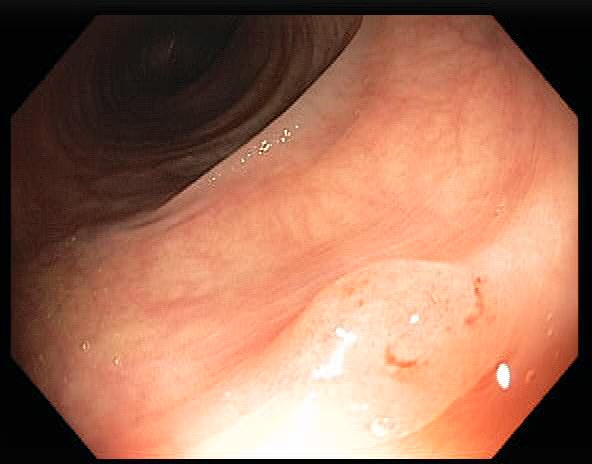

Colonoscopy is the main diagnostic procedure to detect and recognize polyps located on colorectal walls. The accurate detection and correct classification depend on the skills and experience of the endoscopists, however, even for experienced endoscopists, working on conventional colonoscopy for long hours leads to mental and physical fatigue and degraded analysis and diagnosis. Other factors that may affect the classification results include varying illumination conditions, variant texture and appearance, and occlusion. Moreover, different types of polyps are hard to differentiate since they may exhibit a very similar appearance with a subtle difference, as shown in Fig 1. It requires a thorough examination of fine details to distinguish one category form the other. Therefore, an accurate and effective automatic computer-aided system for colonoscopy is required to help endoscopists to detect and classify the type of polyps. This automated recognition mechanism can also be used as a second opinion to determine whether a further biopsy is required for diagnosis, which in turn will greatly reduce the cost of diagnosis. In addition, such an intelligent system can also be used as an educational resource for gastroenterology trainees to reduce the learning curve and cost.

![]() |